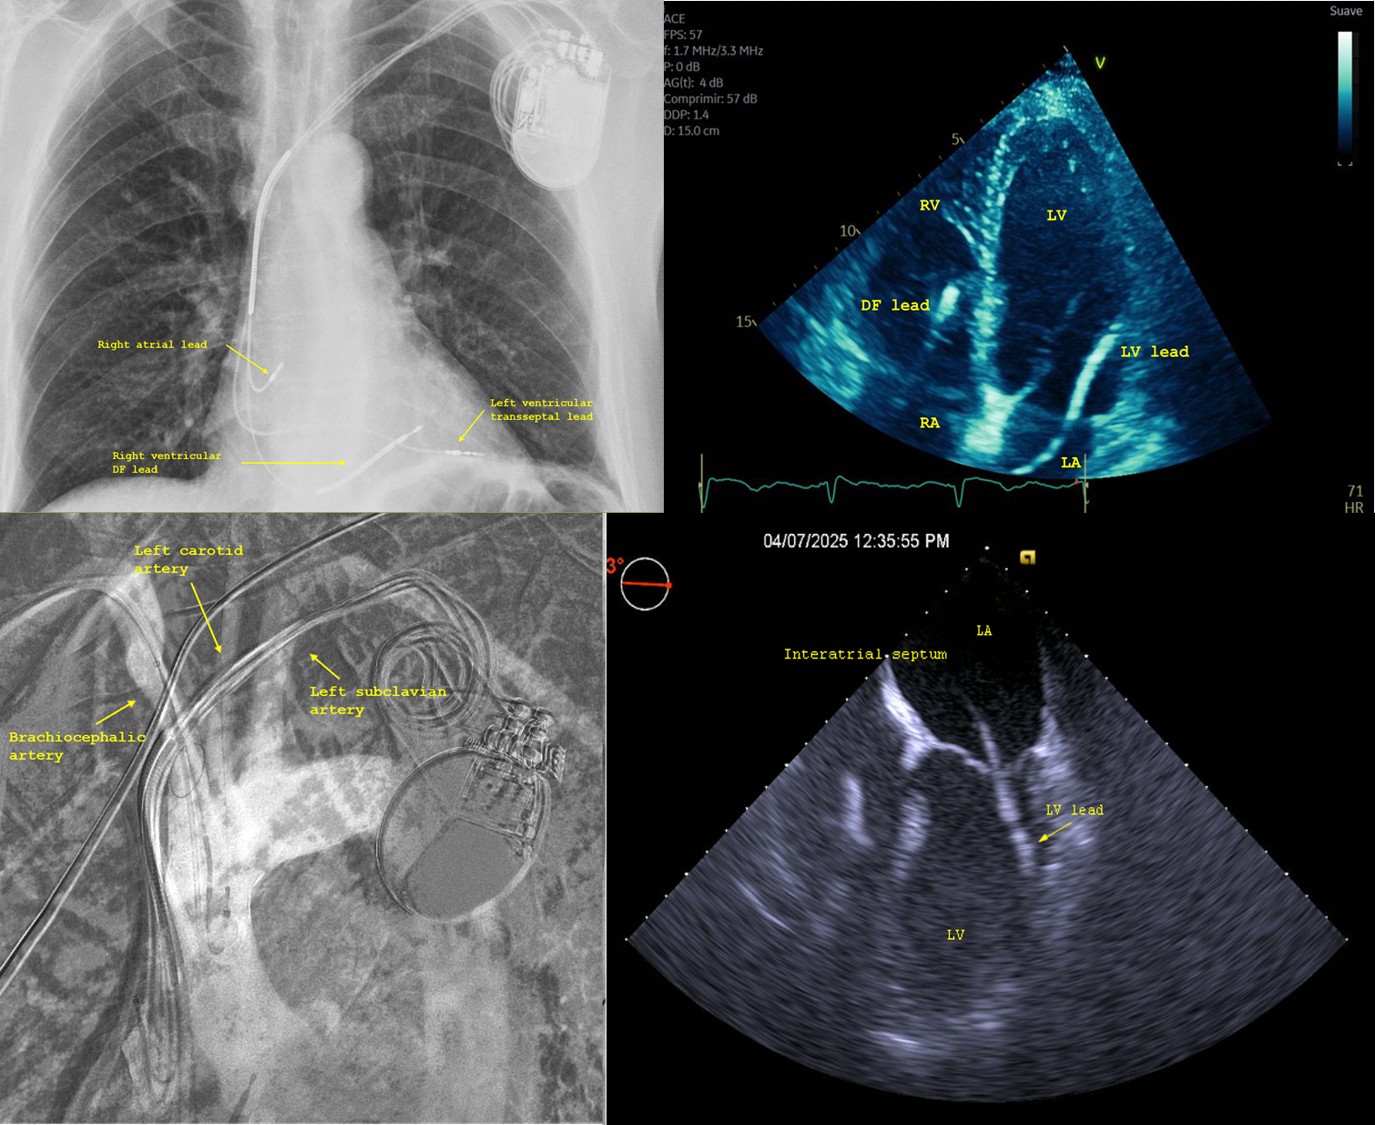

Endocardial left ventricular (LV) pacing through an atrial transseptal approach ...